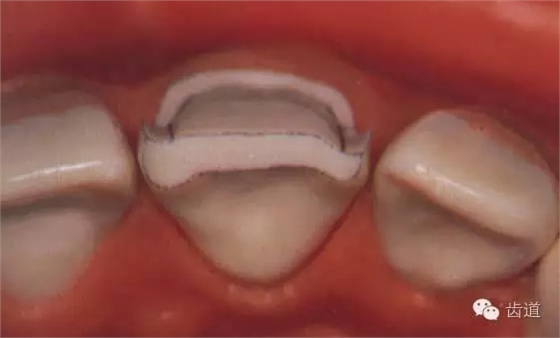

切端面:為瓷粉提供所需間隙,從切端延展到牙面的1/2—2/3

2mm間隙,上前牙切端形成向舌側(cè)傾斜45度角的切斜面;下前牙切端形成向唇側(cè)傾斜45度角的切斜面